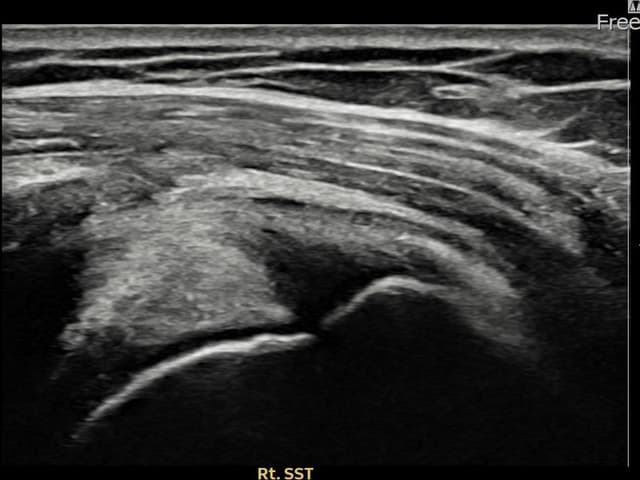

左侧 冈上肌腱 石灰化肌腱炎

9mm × 7mm